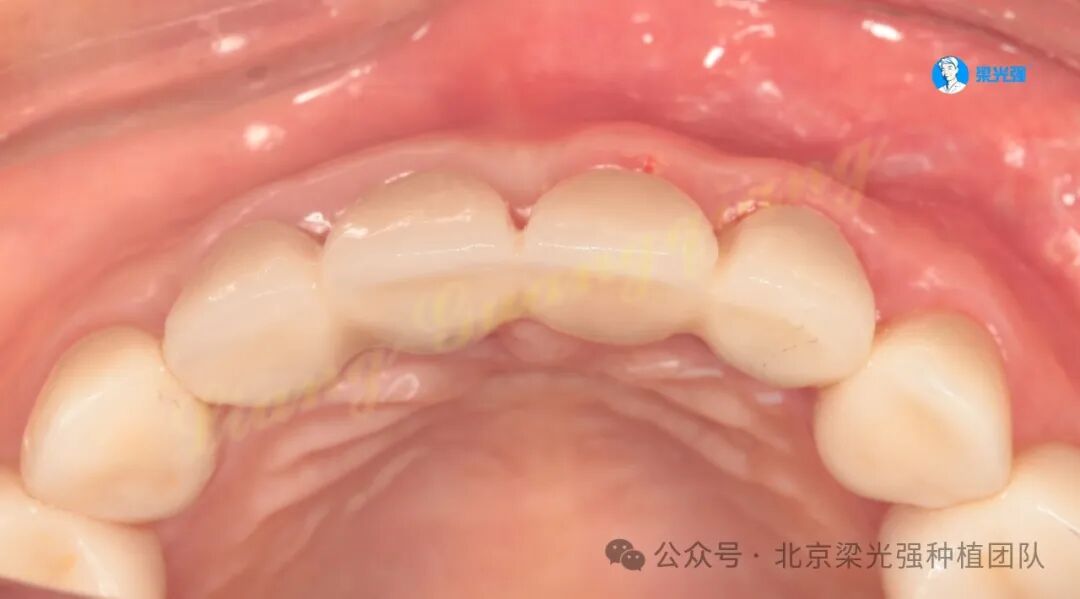

两周后,12-22临时固定修复,牙龈塑形:

两周后修改临时牙的龈缘形态和邻接点位置。

一个月后永久修复。